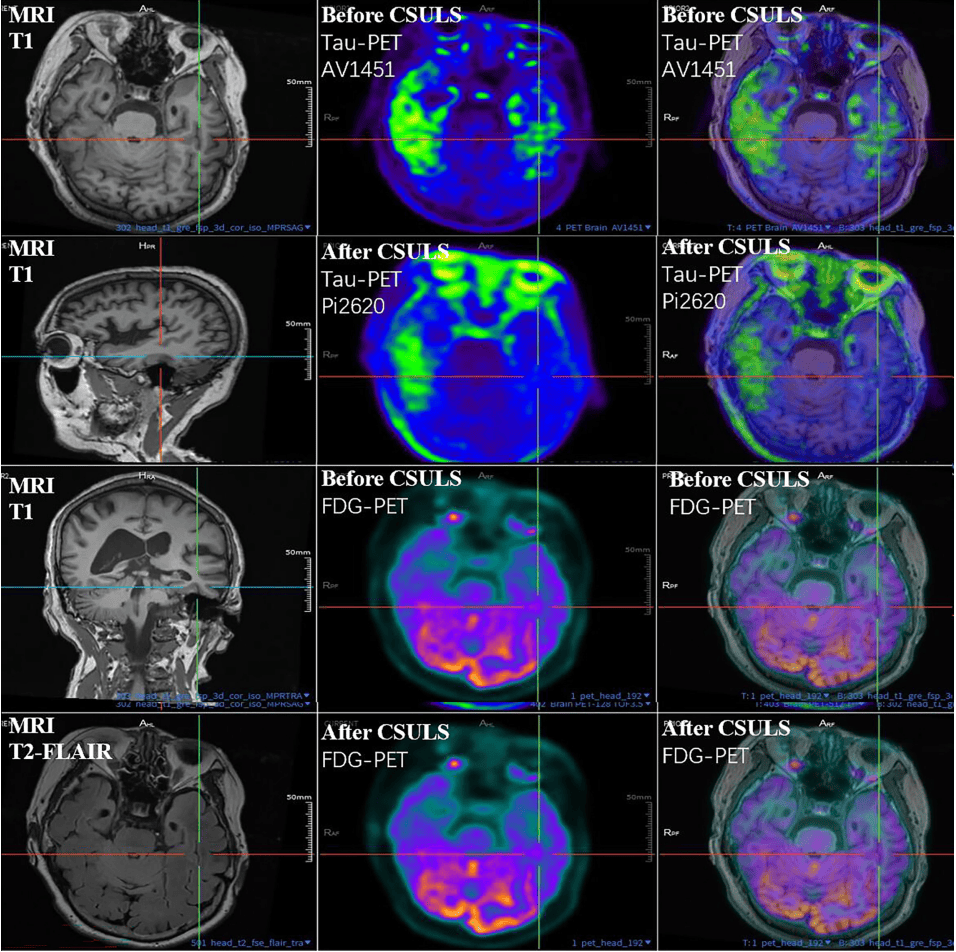

这种积极效果,不是指回光返照式的逆转病情,而是在一年的时间后,从量表评分、生物指标上来看,病情没有进一步进展,“还有极个别患者出现了客观指标的下降”。

任振虎团队发表的一篇文章报告,一位患者颈部淋巴外科术后5周后,整体大脑tau蛋白沉积减少。图为术前术后扫描结果对比。